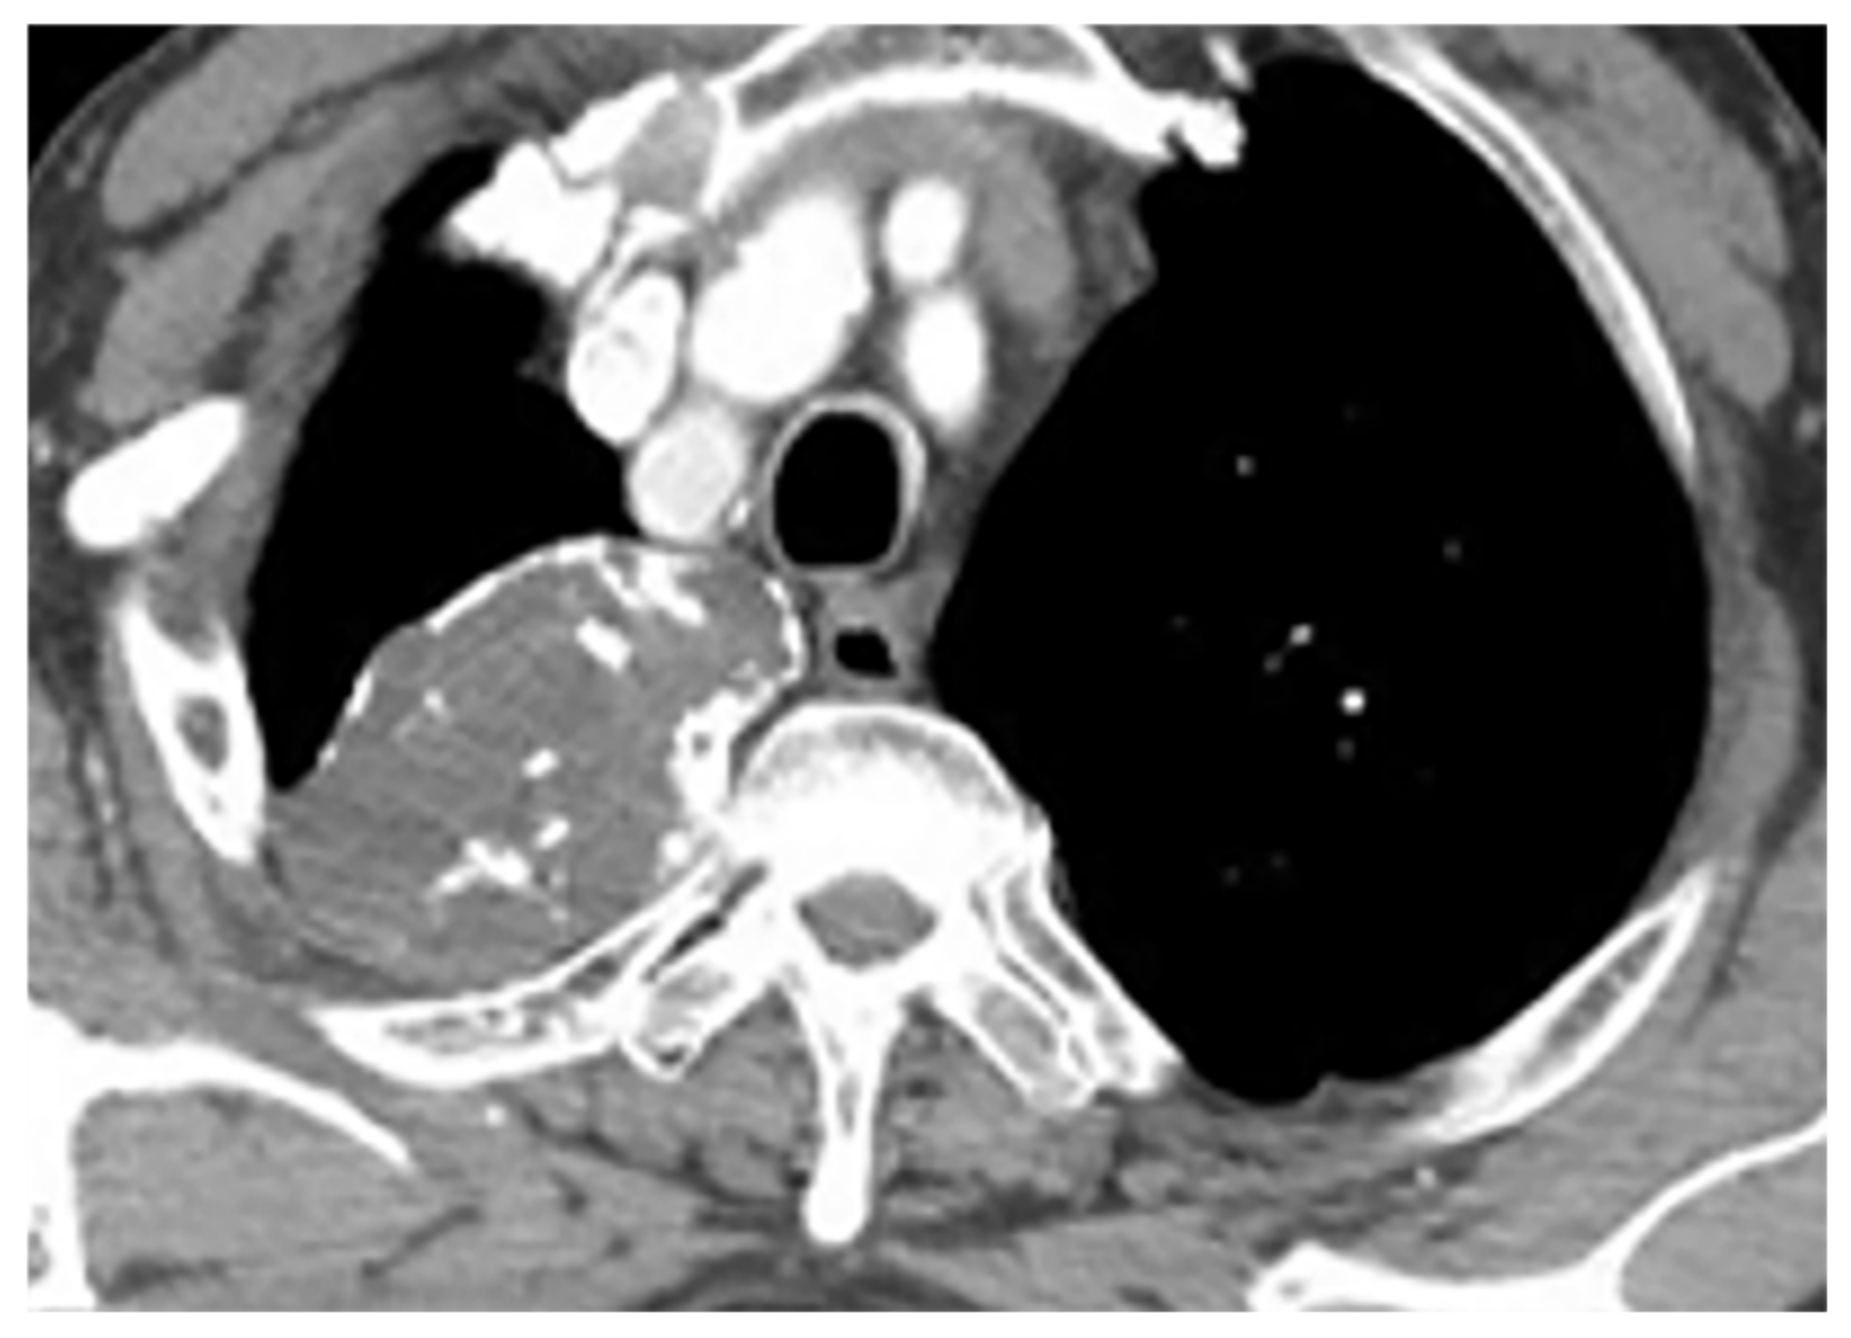

| Mesothelioma | Circumferential pleural thickening, bony or cartilaginous differentiation, unilateral pleural effusion, interlobular septal thickening, tumoral extension, thoracic and extrathoracic metastasis. | T1W: unilateral hyperintense pleural effusion, iso to slightly hyperintense pleural thickening T2W: moderately hyperintense T1WFS + C: typical enhancement is expected |

| Empyema necessitance | Connection of pleural collection to extrapleural mass, soft tissue inflammation, rib destruction with periosteal reaction, and fluid collection. | T1W: hypointense effusion and fluid collection T2W: hyperintense effusion, increased thickness of extrapleural fat, and chest wall muscles with hyperintense on T2WFS T1WFS + C: pleural and septal enhancement |